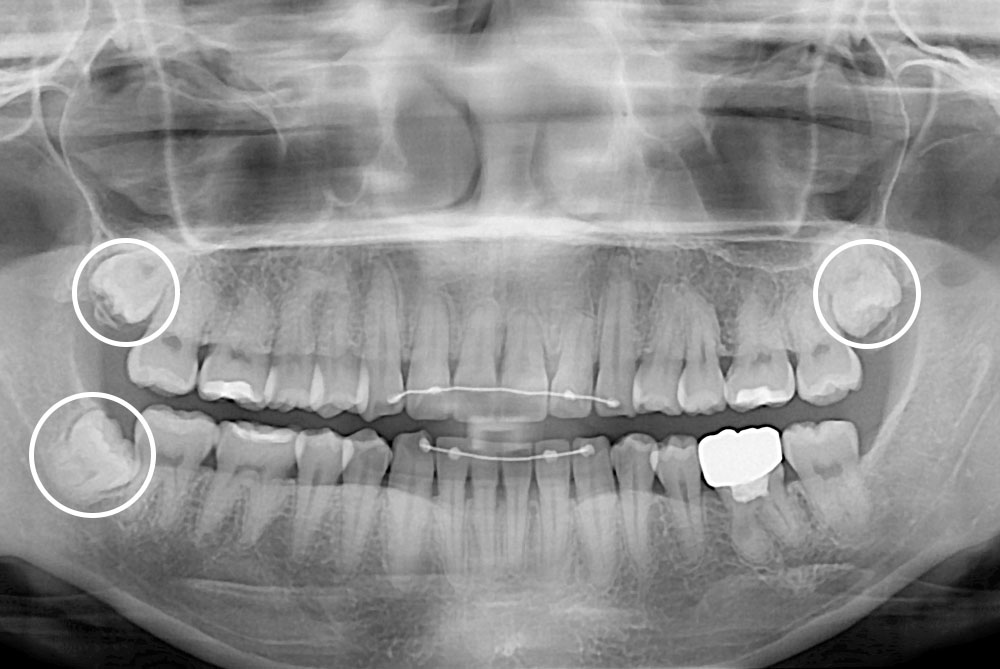

[사랑니] 매복 사랑니 발치

치료전 : 2018-09-28